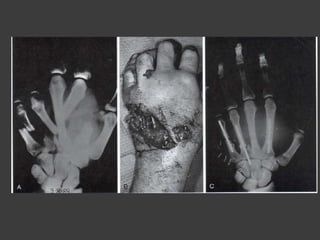

Tratamiento quirurgico

(indicación)

 Falla del tto conservador

 Fracturas expuestas

 Fracturas de 2 o más MTC

 Fx articular desplazada

 Fx con rotación

 Fx con acortamiento > a 3mm

 Fx angulada>10-20°

Complicaciones de las fx

MTC

 Consolidación visiosa.

 Angulación dorsal.

 Malrotación.

 Consolidación defectuosa intraarticular

 Osteomielitis.

 Pseudoartrosis